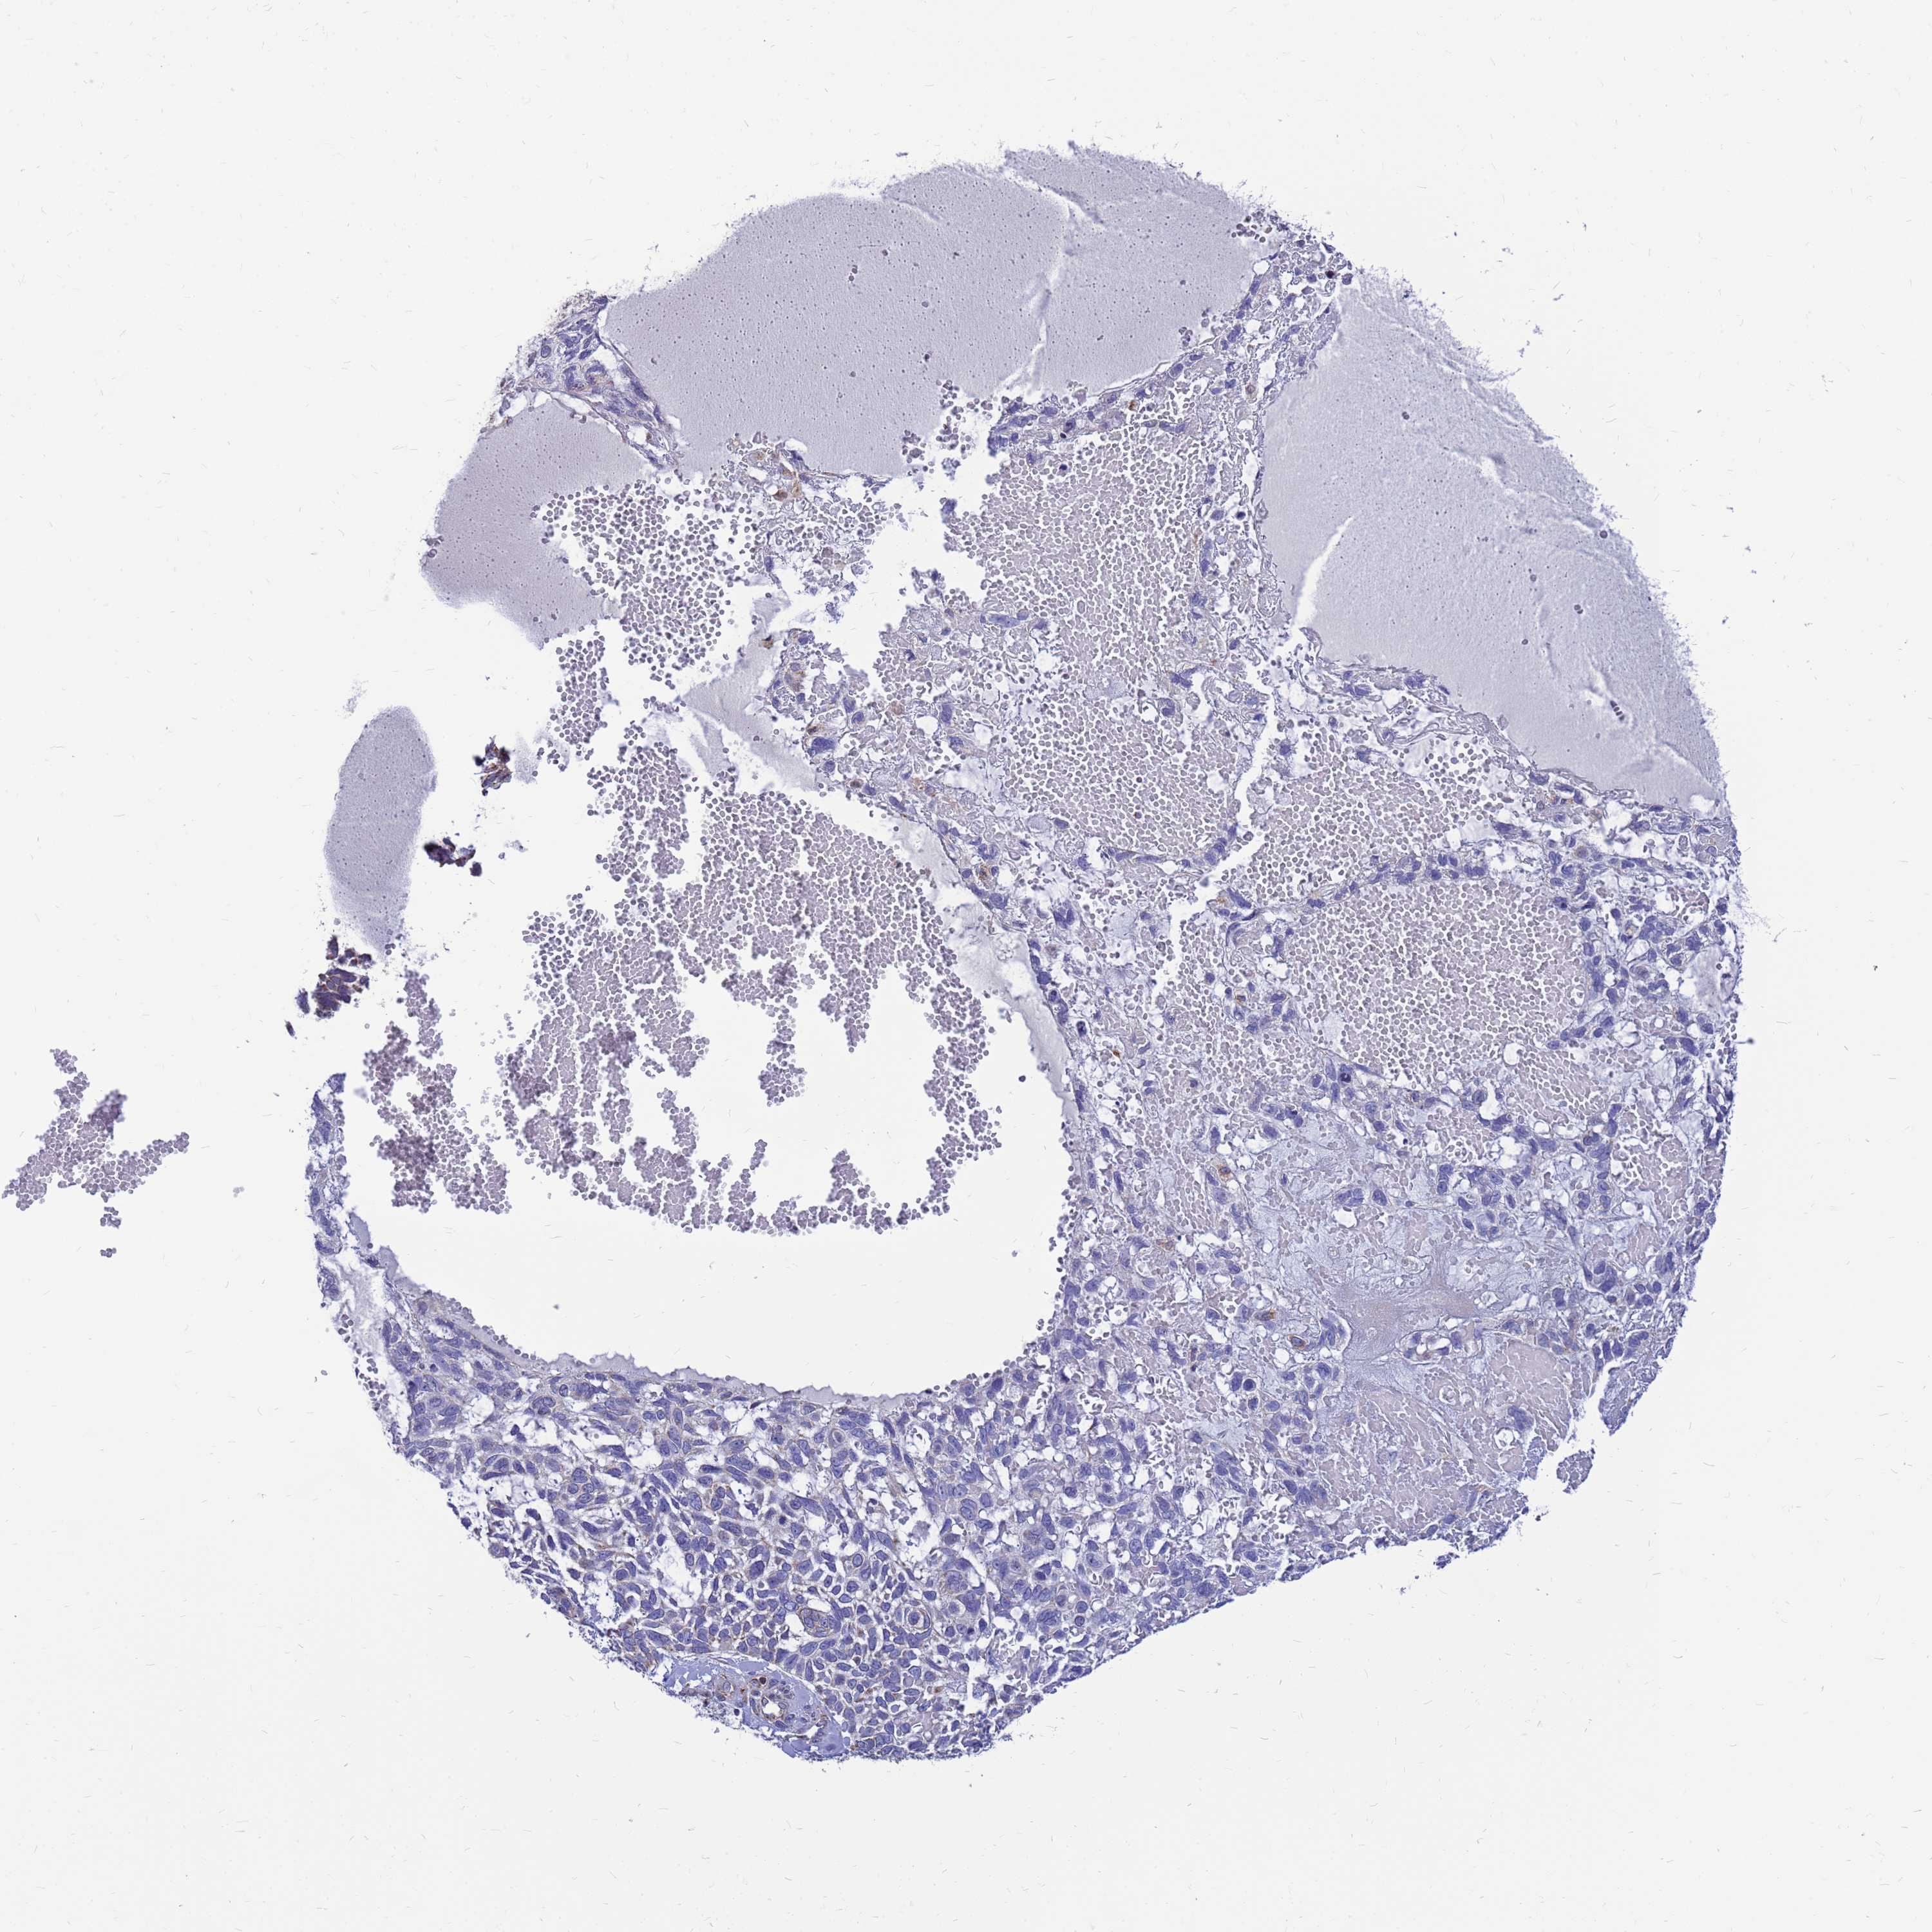

Basal cell and squamous cell cancer

SKIN CANCER - Protein expressioni

A mouse-over function shows sample information and annotation data. Click on an image to view it in a full screen mode. Samples can be filtered based on level of antibody staining by selecting one or several of the following categories: high, medium, low and not detected. The assay and annotation is described here.

Antibody stainingi

Antibody staining in the annotated cell types in the current human tissue is reported as not detected, low, medium, or high, based on conventional immunohistochemistry profiling in selected tissues. This score is based on the combination of the staining intensity and fraction of stained cells.

Each image is clickable and will lead to virtual microscopy that enables deeper exploration of all samples and also displays staining intensity scores, fraction scores and subcellular localization as well as patient and tissue information for each sample.

Antibody HPA045866

Staining

High

Medium

Low

Not detected

Intensity

Strong

Moderate

Weak

Negative

Quantity

>75%

75%-25%

<25%

None

Location

Nuclear

Cytoplasmic/membranous

Cytoplasmic/membranous,nuclear

Basal cell carcinoma